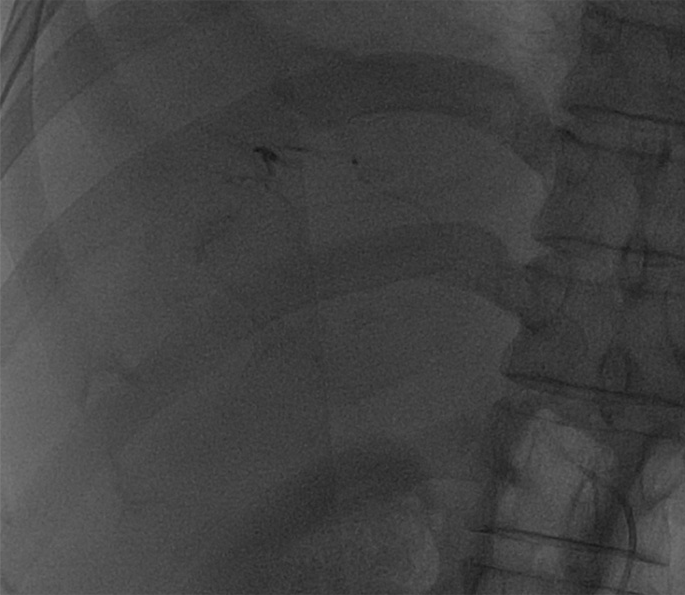

入院后,为患者给予补液,在局部麻醉下行DSA引导下经导管肝肿瘤动脉栓塞术。